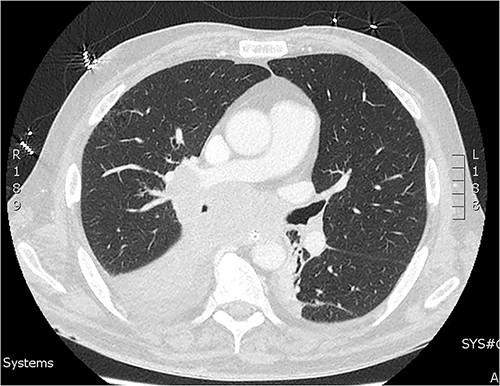

On day two of post laparotomy, a CT chest was performed for disease staging (Fig. 2). This study demonstrated a bulky multi-station mediastinal lymphadenopathy contiguous with soft tissue thickening enveloping the right lower lobe and middle lobe bronchi, suggestive of a primary lung cancer. Extubation was attempted on day three post laparotomy, however, the patient desaturated and was re-intubated and ventilated. Following family discussion regarding the poor prognosis care was withdrawn day six and the patient passed away.

CT of the chest from day two admission demonstrating soft tissue mass enveloping the right bronchi.